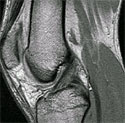

Μαγνητική τομογραφία

Φυσιολογικός οπίσθιος χιαστός συνδεσμός